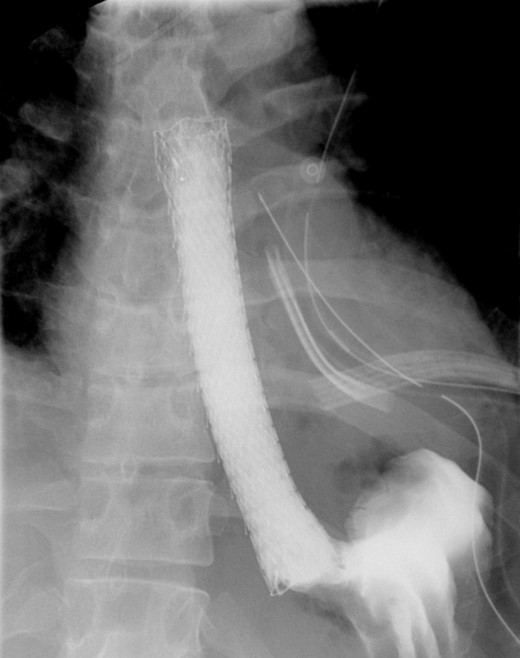

A follow-up EGD was performed 6-weeks later for stent removal. Although the stent had migrated slightly, it continued to cover the previous perforation site. The stent was removed, and the esophagus appeared well healed with no residual tear. Contrast study showed no residual leak or significant stricture (Fig. 4). On follow-up endoscopy, biopsies from the proximal and distal esophagus revealed 20 eos/hpf and 30 eos/hpf, respectively. The patient was kept on PPI and started on topical steroids and continued to do well with no reported symptoms on the last follow up 9 months and two years and a half after the initial presentation.

Shows interval removal of the esophageal stent with no evidence of an esophageal leak.